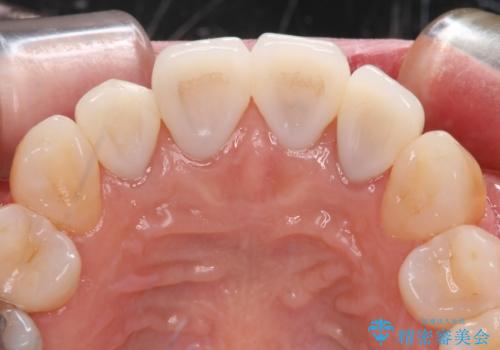

- 上顎4前歯に装着されているセラミッククラウンのうち、ひとつが欠けてしまったとのことで来院された患者様です。

土台となっている歯には問題がないため、周囲のセラミッククラウンと色調が合うように、オーダーメイドタイプのセラミッククラウンにて補綴治療を行うこととしました.

欠けてしまったセラミッククラウンはガラス系セラミッククラウンであったため、今回製作する歯は、強度の強いジルコニアセラミッククラウンとしました。

クラウンの種類は異なりますが、色調の適合したクラウンを装着することができました。